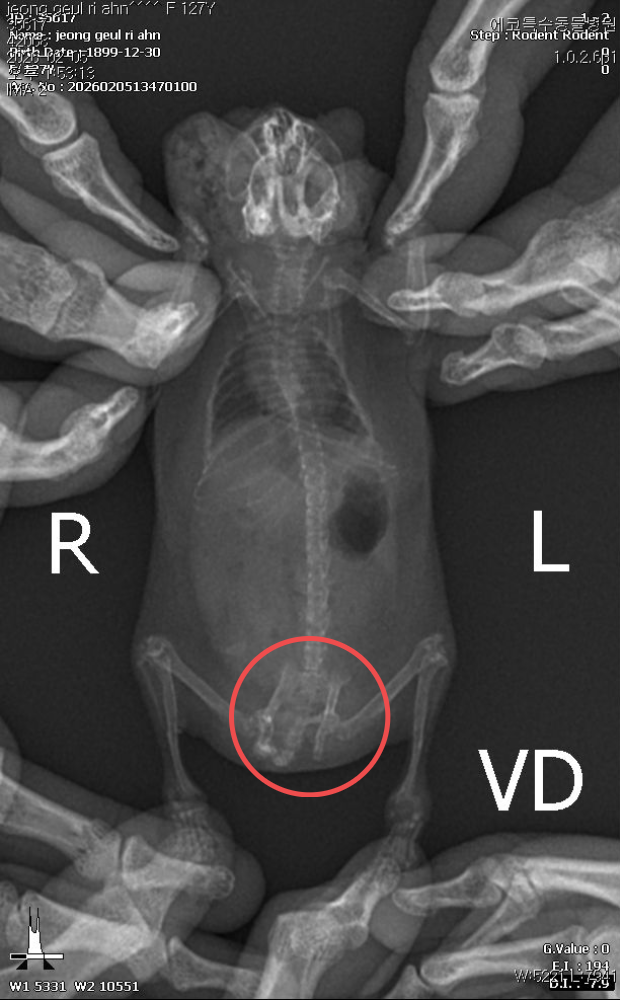

○ 이어 "귀가 찢어지는 등 다수의 개체에서 교상 흔적이 관찰됐으며, 일부 개체는 장기간 반복된 타박상으로 인해 골절 및 재골절이 의심되는 정황까지 확인됐다"고 덧붙였다.

<외부 충격 의심되는 골반 골절 흔적 엑스레이 사진_정글리안 햄스터>